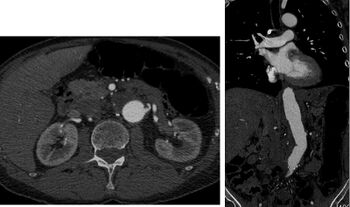

CT angiography (CTA) is highly effective for evaluation of the arterial system, and has largely replaced conventional angiography due to the lower risk profile and ability to survey the entire abdomen. Images are acquired after a rapid bolus of intravenous contrast material (3-7 cc/s) during the arterial phase (15–35 seconds after injection) when the concentration of contrast material in the arterial system is high (figures 3). Images are usually acquired using narrow collimation (<1 mm) and can be retrospectively reconstructed using dedicated 3-dimensional workstations and software. CTA is commonly used in the head and chest in the evaluation of pulmonary emboli, aneurysms, vascular malformations, dissection, bleeding and ischemia. Indications for early arterial phase imaging include: evaluation of aneurysms or dissections (cerebral, aortic, etc.), hepatic, splanchnic or renal arterial anatomy, and arterial imaging in liver or kidney transplantation. Single phase arterial imaging is often used in the evaluation of trauma patients either a complete chest/abdomen/pelvis examination with arterial phase imaging of the chest and portal venous phase imaging of the abdomen/pelvis or just a portal venous phase of abdomen and pelvis depending on the mechanism and severity of the trauma. CTA is also commonly performed in the abdomen and pelvis for evaluating vascular malformations and in the evaluation of bleeding. Mesenteric ischemia can also be evaluated using CT angiography. CTA of the abdomen and pelvis is often performed in combination with a CTA for evaluating the extremity vasculature.[citation needed]